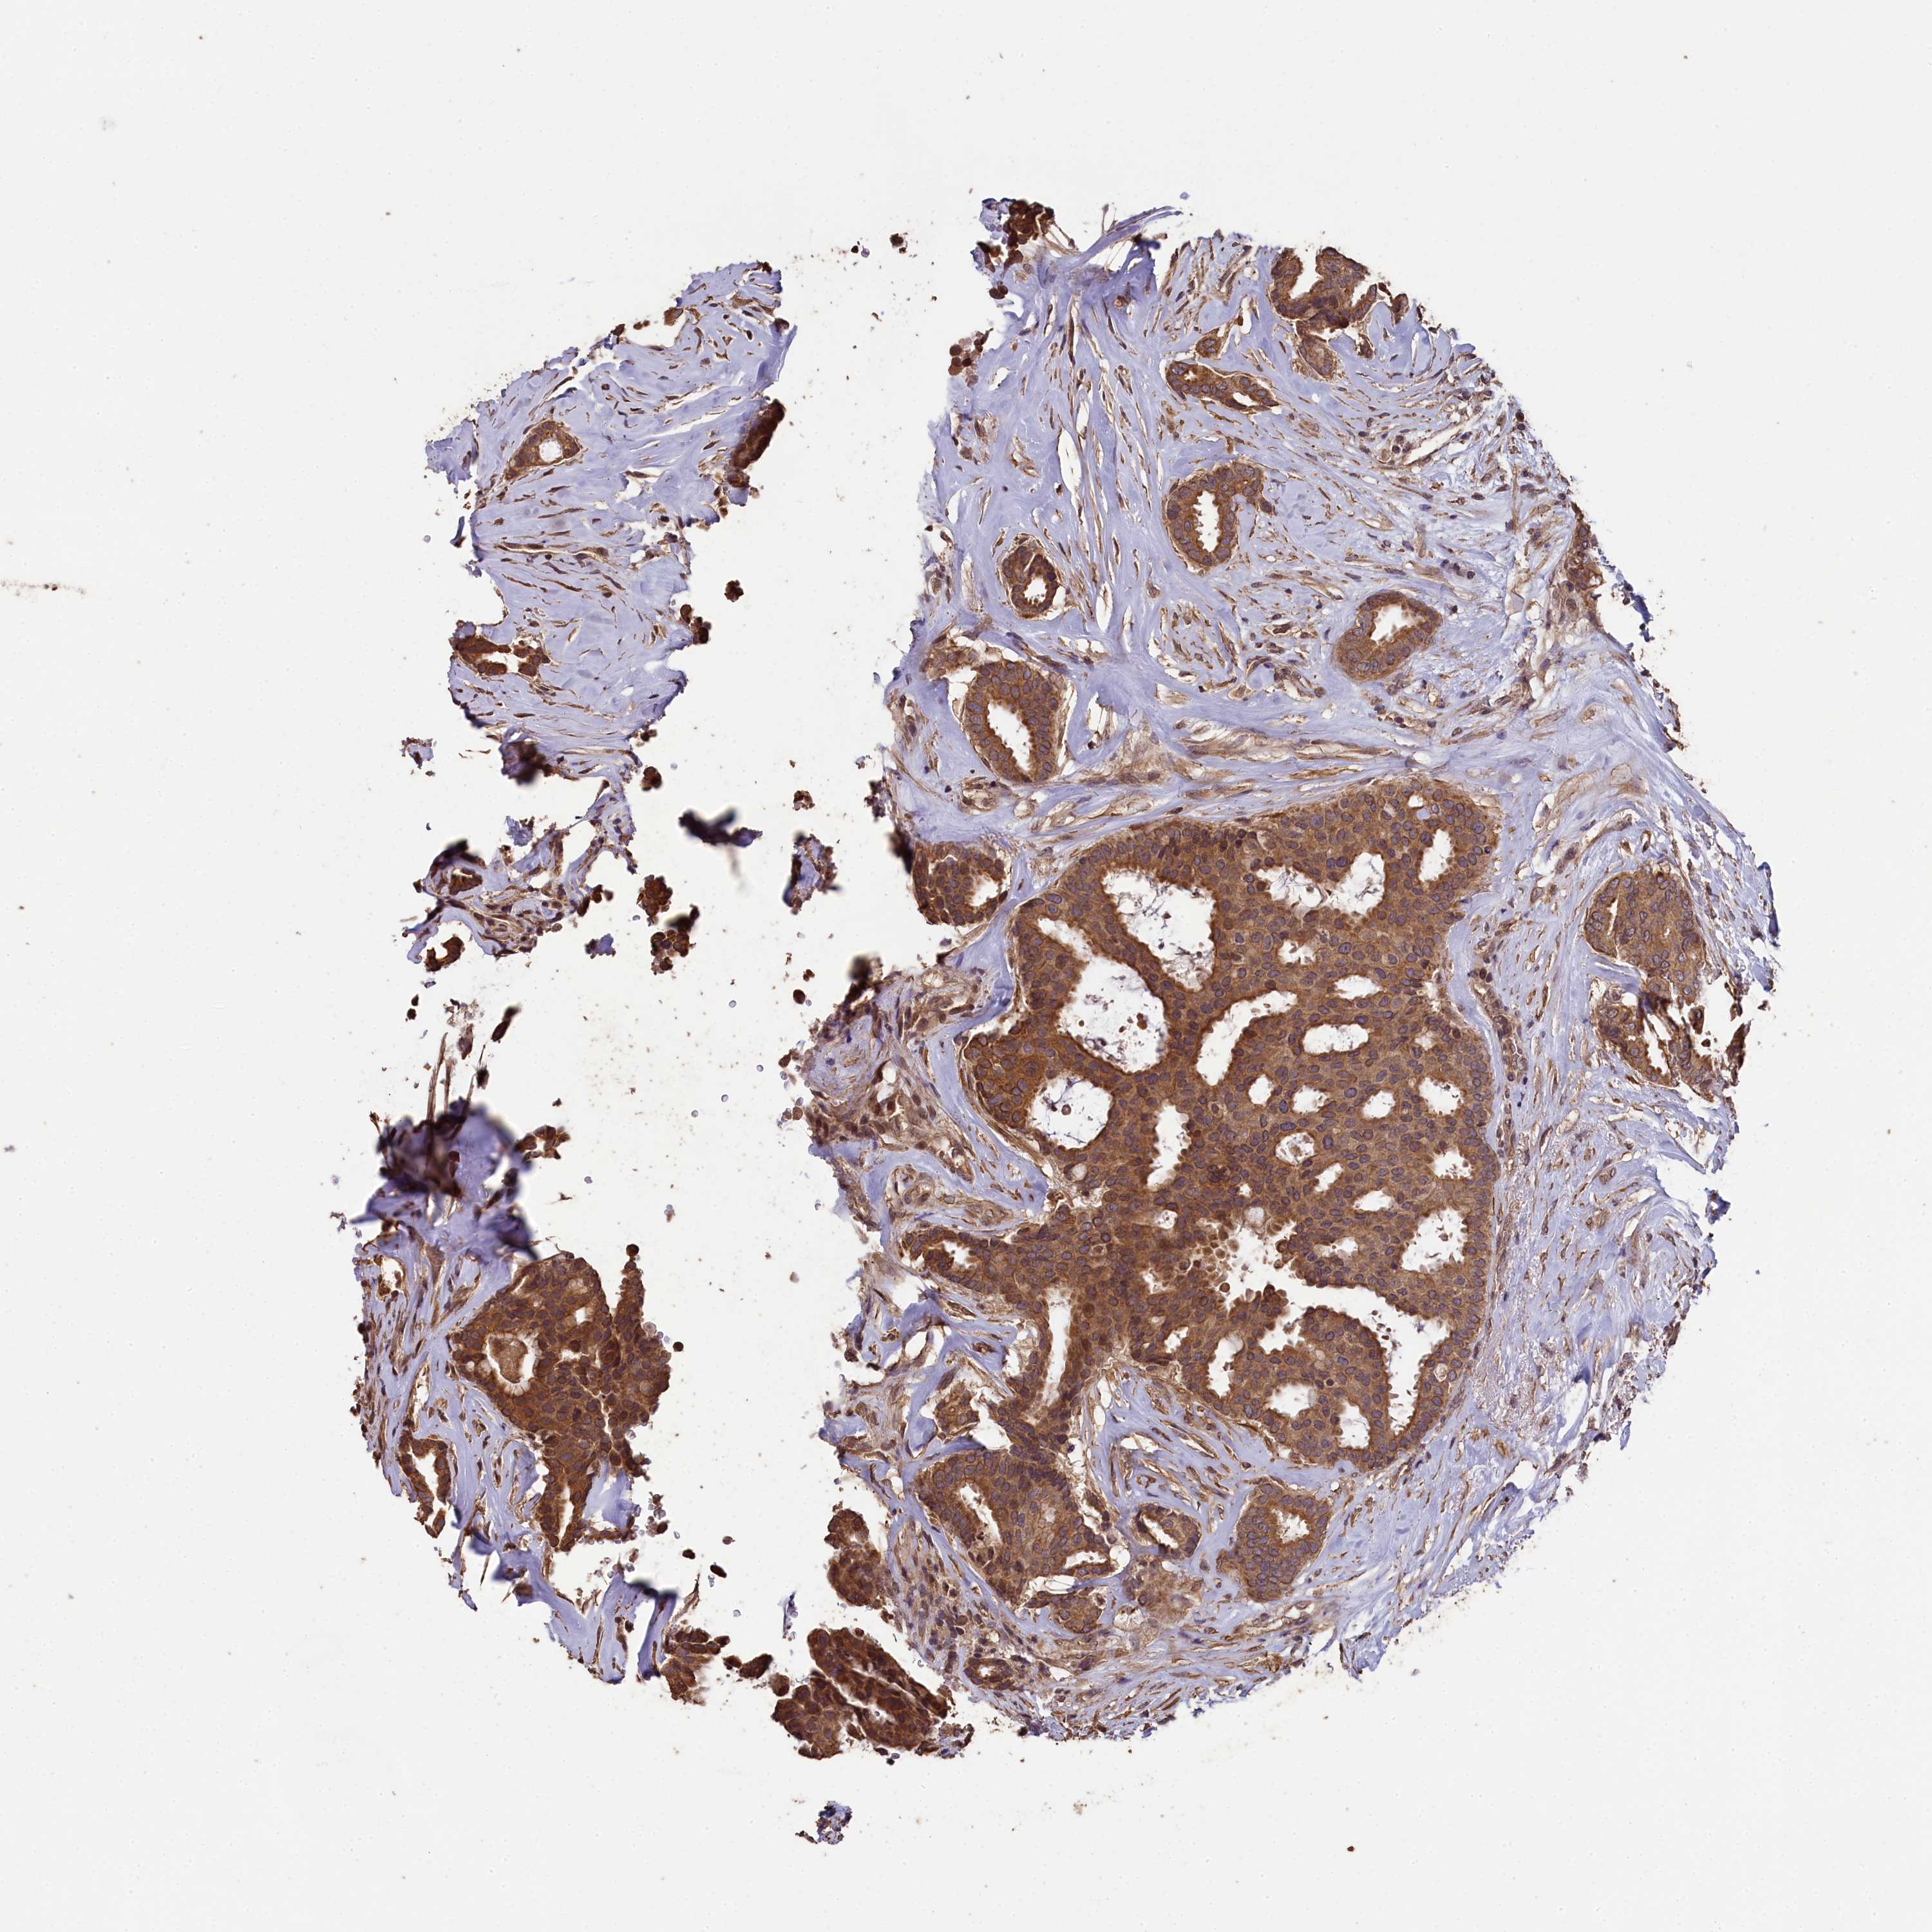

BRCA TCGA BRCA VALIDATION PROTEIN EXPRESSION

ANTIBODIES

AND

VALIDATION